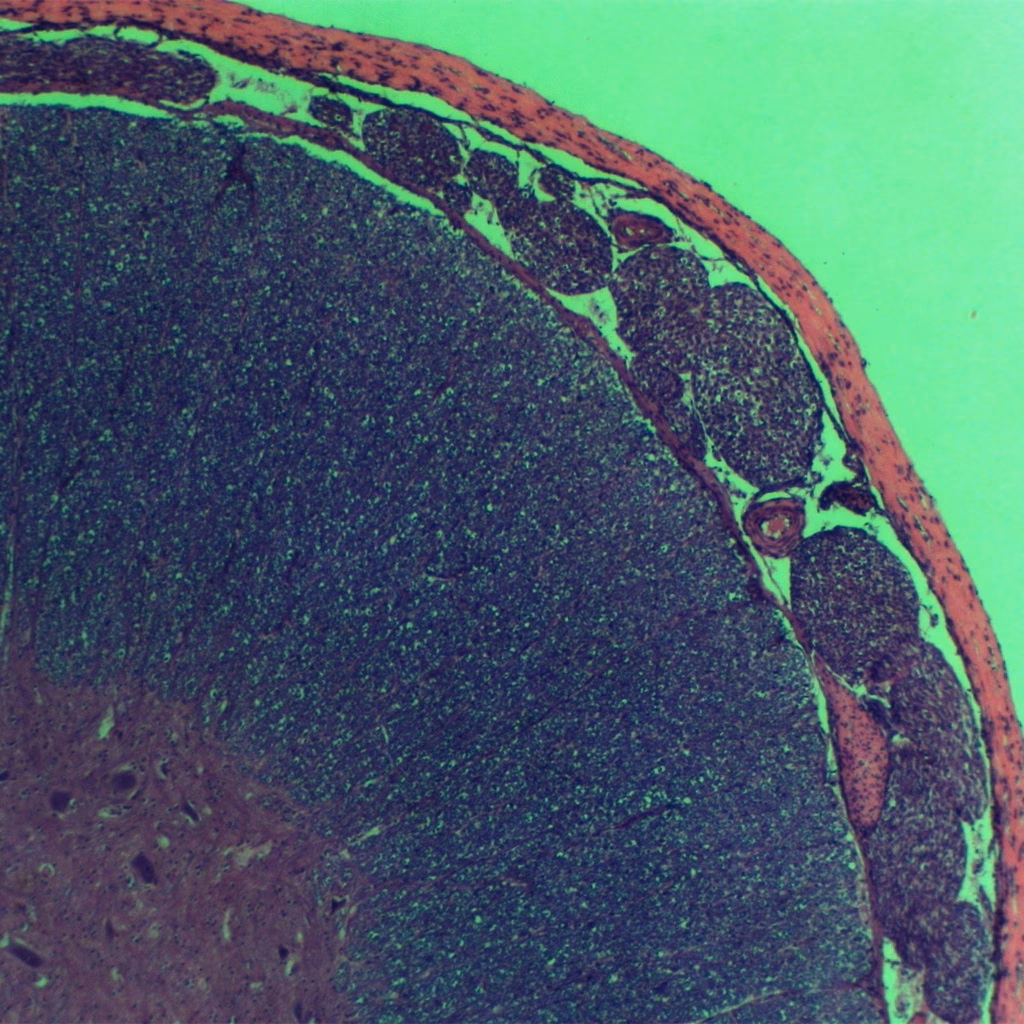

La médula espinal es una estructura fascinante y fundamental en el sistema nervioso de los conejos, al igual que en muchos otros animales. Constituye una parte esencial del sistema nervioso central, trabajando en conjunto con el cerebro para coordinar una vasta red de funciones corporales. Comprender qué es y cómo funciona nos ayuda a apreciar la delicadeza de su anatomía y la importancia de su protección.

En esencia, la médula espinal es un denso haz de fibras nerviosas. Su función principal es actuar como un puente de comunicación, enlazando el cerebro con el resto del cuerpo. Esta conexión bidireccional permite que las señales y mensajes viajen desde el cerebro hacia los músculos y órganos, y que la información sensorial retorne al cerebro. Es la autopista principal por la que transita la información vital para el movimiento, la sensación y muchas funciones automáticas.

Formando, junto con el cerebro, lo que se conoce como el sistema nervioso central (SNC), la médula espinal es una estructura delicada que requiere una protección robusta. Afortunadamente, la naturaleza le ha proporcionado una defensa sólida: está protegida por la columna vertebral, una serie de huesos (vértebras) que la rodean y salvaguardan de impactos y presiones externas. En el conejo, esta protección es crucial dada su anatomía y movimientos.

La médula espinal se extiende desde la base del cerebro hacia abajo a través del canal vertebral. A lo largo de su recorrido, los nervios espinales se ramifican para alcanzar todas las partes del cuerpo, desde las patas hasta los órganos internos. Esta organización permite que el cerebro mantenga el control y la comunicación con prácticamente todo el organismo.